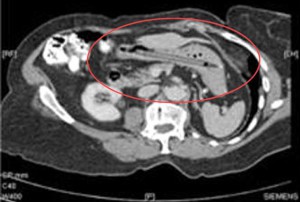

Pero cuando los médicos le hicieron escáner de su vientre notaron algo extraño: un rotulador por allí danzando.

25 años después los médicos lo han encontrado justo donde la señora decía que estaba. Y aunque no era la causa de sus males gastrointestinales, han decidido quitárselo para evitar la posibilidad de una perforación del intestino.